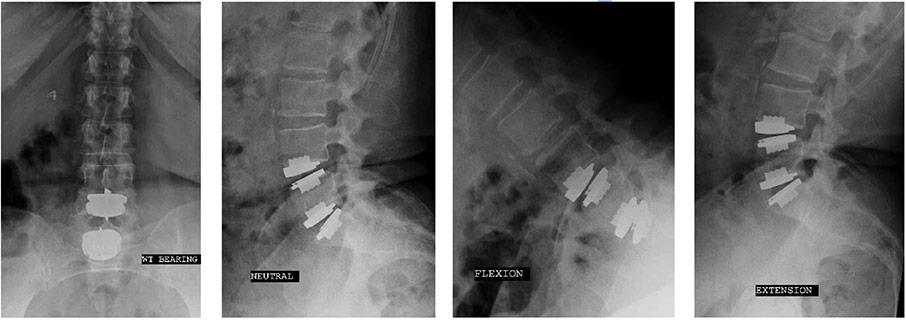

prodisc L Gallery

Click to enlarge image